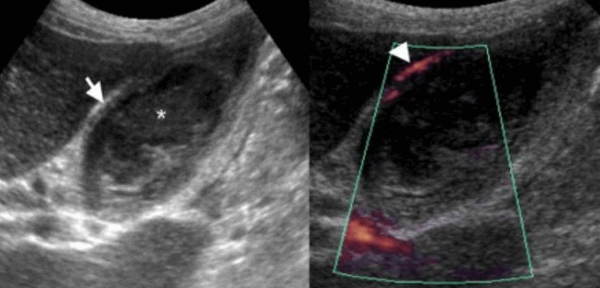

УЗИ некалькулезный холецистит.

Острый бескаменный холецистит возникает у пациентов во время поста, а также у пациентов, которые принимают лекарства, вызывающие холестаз. К признакам некалькулезного холецистита относятся все признаки острого калькулезного холецистита кроме наличия камней в просвете желчного пузыря, но при этом взвесь обычно присутствует.

74 — летнему мужчине выполнено УЗИ желчного пузыря. Диагноз: острый некалькулезный холецистит. На левой сонограмме стрелкой указано утолщение стенок желчного пузыря. В просвете желчного пузыря взвесь. На правой сонограмме у того же пациента при исследовании в доплеровском режиме выявлен еще один признак воспаления — гиперемия.